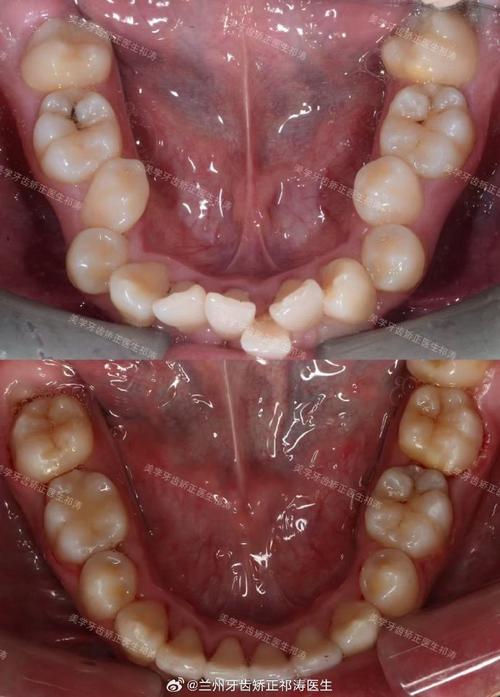

只拔上颌正畸主要适用于上颌牙量与骨量不匹配、下颌排列相对正常的患者,具体包括:上颌牙齿中度至重度拥挤(如牙弓长度不足7mm)、上颌前突(深覆盖,上切牙唇倾明显)但下颌位置正常、上下颌骨关系基本协调(非骨性畸形)、患者对美观改善需求迫切(如希望改善“龅牙”),其核心逻辑是通过拔除上颌特定牙齿(通常为第一前磨牙),为拥挤牙齿提供排齐空间,或通过前牙内收改善前突,同时避免对下颌牙列的过度干预,减少下颌前牙舌倾、后牙升高或咬合干扰等风险。

拔牙选择需兼顾间隙需求与功能稳定,上颌首选拔除第一前磨牙(4号牙),原因在于:该牙位于牙弓中段,拔除后可提供约5-7mm间隙,既能有效解除拥挤,又能通过前后牙的支抗控制(如使用支抗钉或滑动法关闭间隙),避免前牙过度内收导致牙根吸收或牙龈凹陷,相较于上下颌联合拔牙,只拔上颌的优势在于:减少治疗创伤(仅一次拔牙手术)、简化支抗设计(无需同时控制上下颌支抗)、降低下颌牙列移动的复杂性,尤其适合下颌本身无明显问题、仅需调整上颌的患者,对于成年患者,该方案可缩短治疗周期(通常减少3-6个月),且对面部垂直高度的影响更小。